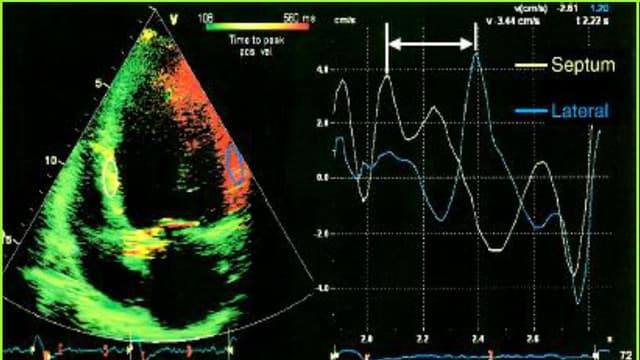

Các chỉ số trong siêu âm Doppler tim phản ánh trực tiếp cấu trúc, chức năng co bóp và khả năng bơm máu của tim. Tuy nhiên, không phải người bệnh nào cũng hiểu rõ ý nghĩa của những ký hiệu và thông số xuất hiện trong kết quả siêu âm. Việc nắm được cách […]

Siêu âm doppler tim là phương pháp giúp khảo sát sự biến đổi hình thái, chức năng và huyết động của tim thông qua hiệu ứng doppler, việc sử dụng doppler xung, doppler liên tục, doppler màu. Vậy khi nào cần siêu âm doppler tim? 1. Siêu âm doppler tim là gì? Siêu âm Doppler […]

Siêu âm doppler tim là chỉ định cần thiết trong chẩn đoán và đánh giá các bệnh lý tim mạch. Vậy siêu âm doppler tim là gì? 1. Siêu âm Doppler tim là gì? Siêu âm Doppler tim là một thăm dò chẩn đoán hình ảnh giúp chẩn đoán tình trạng hoạt động và hình […]